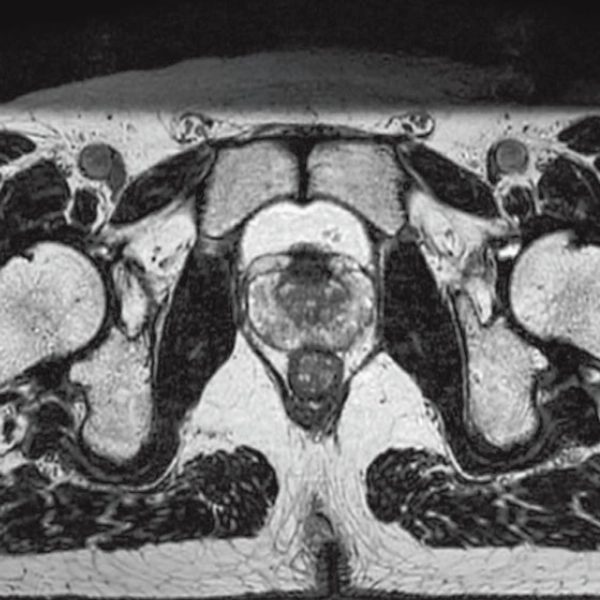

DLR offers 2 options

High Resolution

T2WI, 0.56×0.70×3.0mm, 2:28